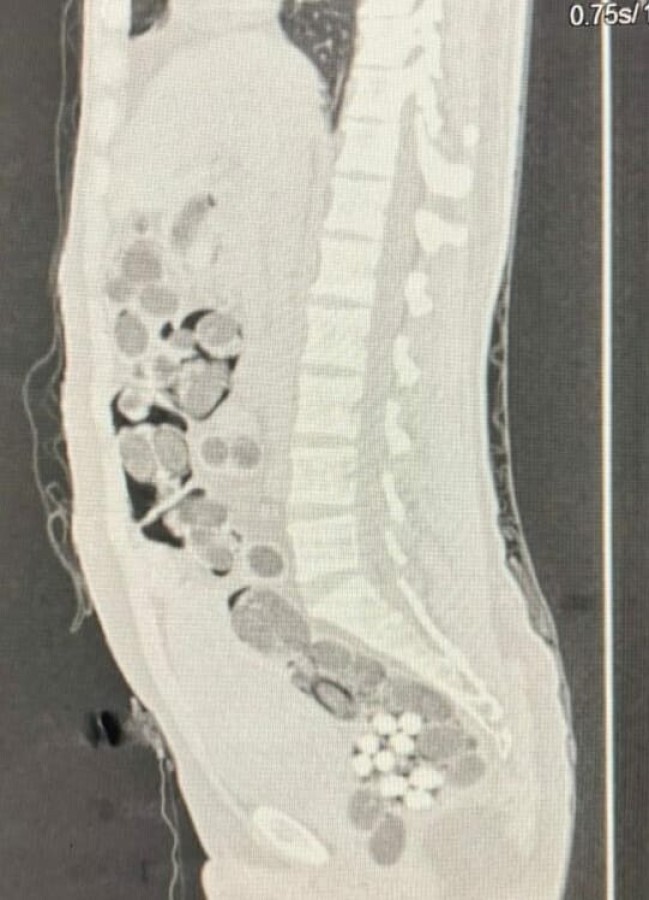

Denizli Devlet Hastanesi'ne götürülüp, röntgeni çekilen yabancı uyruklu şüphelinin midesinden 219 paket halinde 1 kilo 144 gram skunk, 178 gram metamfetamin, 90 uyuşturucu hap ve 7 gram Afyon sakızı çıktı.